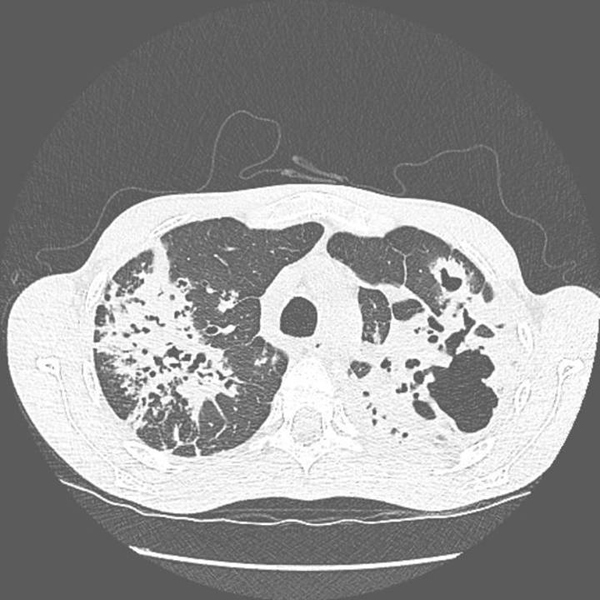

La Revue du Praticien - Hélène Leroy Volumineuses condensations alvéolaires des deux sommets avec multiples cavitations.